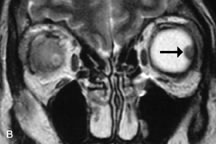

Lymphomas have MRI characteristics similar to those of inflammatory lesions in that they are hypointense to fat and isointense to muscle on T1-weighted images (Fig. 22). They may appear hyperintense to fat on T2-weighted images, perhaps owing to less fibrosis than that seen in orbital inflammatory pseudotumor, although this is not a consistent finding.31,50,66 Lymphoid tumors typically enhance moderately after contrast injection. Unfortunately, studies have shown that tumor density and homogeneity are similar between inflammatory and malignant orbital infiltrates, and MRI cannot differentiate these lesions.72,73

Fig. 22. A and B. T1- and (C) T2-weighted MR scans demonstrate a poorly defined multicompartmental mass enveloping the lateral rectus, superior rectus, and levator palpebrac superioris muscles. The lesion is isointense to brain on T1- and T2-weighted scans, as is typical for highly cellular neoplasms. D. Postcontrast fat-suppressed T1-weighted scan demonstrates intense enhancement of the infiltrating intraconal and extraconal tumor.